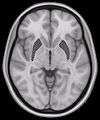

Horizontal slice of MRI-image showing the putamen. The other nuclei of the basal ganglia (caudate nucleus and globus pallidus) can be seen as well.- Putamen